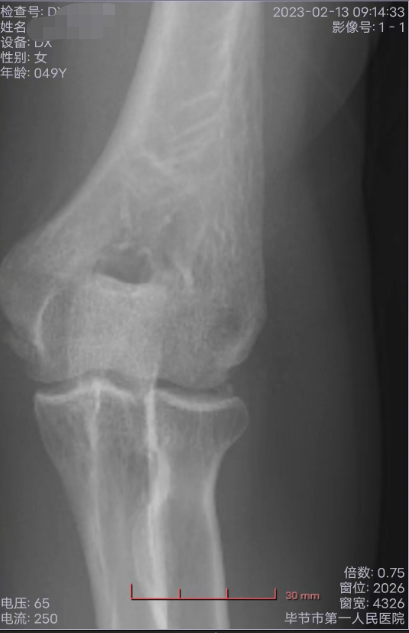

王某在毕节市第一人民医院进行检查

王某将两个儿子的遭遇归因为自己“无能”——2022年,她在意外摔跌后左肩胛骨骨折,手肘骨裂,又因为没有得到及时治疗,导致手肘缺血性坏死,并引发骨囊肿,急需手术,否则面临截肢风险。大儿子急于赚钱,就是为了帮她攒出手术费。